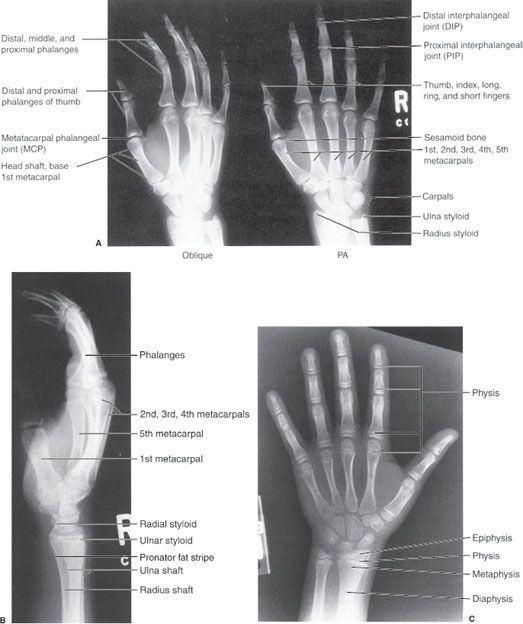

x ray of right hand and wrist

Posts: x ray of right hand and wrist